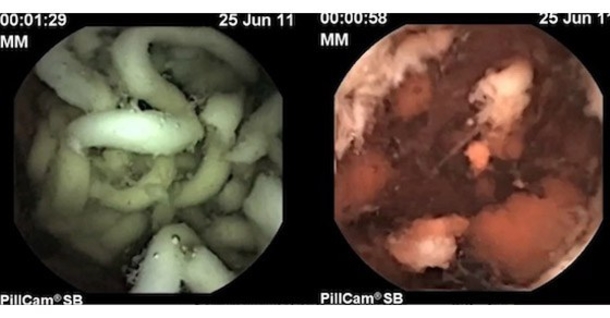

Ramen noodles contain TBHQ a byproduct of the petroleum industry. A gastrointestinal specialist conducted an experiment with a time lapse video inside the stomach comparing both fresh and preserved ramen noodles. He used a tiny camera to study the breakdown of instant ramen noodles in the stomach and found out just how difficult it is for your body to digest the preservative-filled noodles. A gastrointestinal specialist used a time lapse video inside of the stomach to document two hours of digestion. It can also interfere with your blood sugar levels and insulin release if digested too quickly.

Thanks to the smart pill a camera the size of a multi-vitamin Dr. Interestingly it was seen that the stomach took close to a couple of hours to digest and completely breakdown the noodle strains as opposed to freshly made noodles. Braden Kuo At two and four hours the particular size of the ramen noodle was much larger or formed than the homemade ramen noodle at each of those time points suggesting ramen noodles were difficult to break down into an infinite particulate matter during the process of digestion. Ramen actually distresses the digestive tract. He wanted to find out what happened to food in the stomach and digestive tract after consuming ramen noodles.

Looking at the instant ramen noodles after two hours showed that they were much less broken down and almost fully intact. As mentioned earlier ramen noodles lack a. It is used because it prevents the oxidation of fats and oils which. The noodles were found to be intact. A gastrointestinal specialist conducted an experiment with a time lapse video inside the stomach comparing both fresh and preserved ramen noodles.